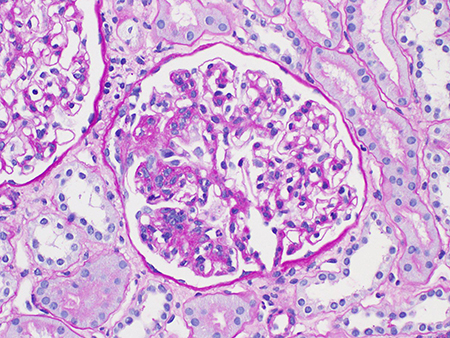

Endocapillary hypercellularity (E0 or E1)[Figure caption and citation for the preceding image starts]: Endocapillary hypercellularity in IgA nephropathy (Periodic acid-Schiff stain, x400)Courtesy of Drs Hwei Yee Lee, Cristine Ding, and Yong Howe Ho (Tan Tock Seng Hospital, Singapore) [Citation ends].